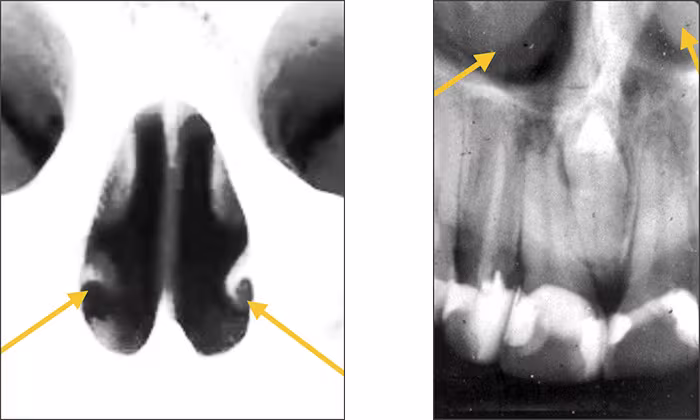

Inferior nasal concha – The inferior nasal concha or turbinate bone projects into the inferior aspect of the nasal fossa from the lateral walls of the nasal cavity. These bilateral radiopaque structures (conchae) are sometimes visible on central and lateral incisor periapical images.

Inverted Y – The inverted Y is a radiographic landmark that depicts where the nasal fossa crosses the maxillary sinus. The boundary between them is shaped like an upside-down letter Y, hence its name. The periapical images below demonstrate the inverted Y, a classic radiographic landmark of the right and left anterior maxilla. The fossa is positioned toward the midline while the sinus extends toward the posterior aspect of the maxilla. Typically, the inverted Y sits apical to the maxillary lateral incisor and canine teeth. No comparable structures are found in the mandibular lateral incisor and canine areas which differentiates maxillary from mandibular anterior periapical images.

Nasal soft tissue – The soft tissue of the nose, including the tip and ala (corner of the nose), often can be seen superimposed over the roots of the teeth on anterior periapical images. The nasal soft tissue appears radiopaque.